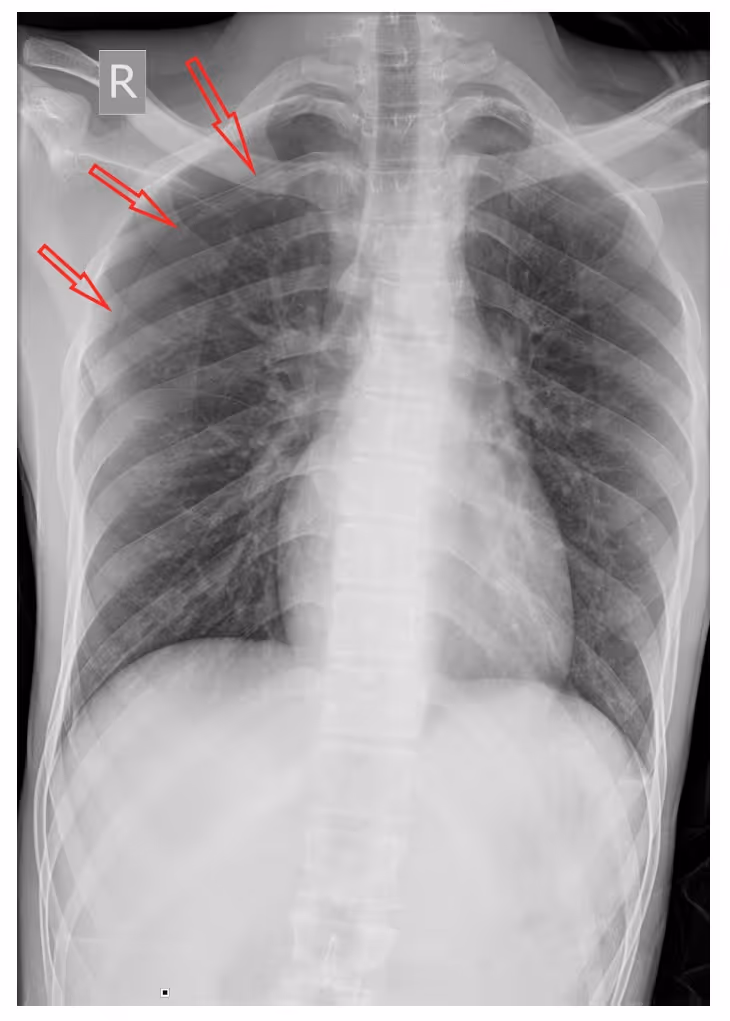

- A frontal chest radiographic image highlights the classic appearance of right-sided pneumothorax with a readily apparent visceral pleural line as seen without distal lung markings